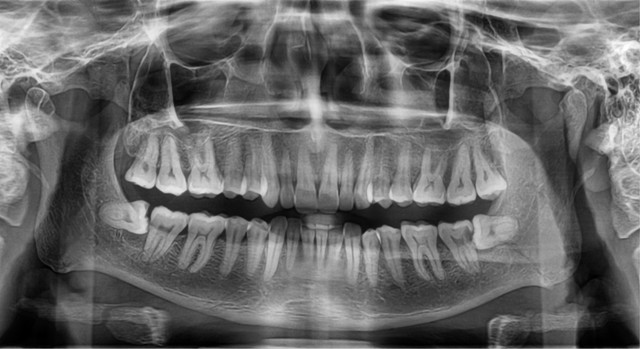

Bad tooth pain but xray showed nothing. If antibiotics help to relieve the pain its very possible you have a low grade or early infection that is hiding on xray those buggers can do that sometimes. Im assuming your Dentist took xrays of the entire upper and lower quadrant where youre having pain – its not uncommon for a painful tooth to send confusing pain signals to teeth in the same quadrant. See an Endodontist.

It could be that the nerve in the tooth is irreversibly damaged causing pressure and therefore the pain. X-rays will not show whether the nerve of the tooth is alive or dead. I would suggest that you see an endodontist who specializes in this area to further evaluate the tooth.

If it is the upper teeth either molars or bicuspids this can cause a throbbing pain in the tooth especially if the roots are either in or close to the sinuses. A fourth cause can be a split in the root of the tooth. This does happen and it is not diagnosable by x-ray.

These minute cracks are often missed on x-rays and need confirmatory tests which are done by. There is a special plastic bar like device available of a particular thickness which your dentist can place in your mouth. If you bite on that and there is a sudden sharp shooting pain which indicates crack.

This on and off thing went on till about 2 months ago. Very often one can have tooth pain from a microscopic crack in a tooth that will not show up on an x-ray. Diagnostic test like percussion endo ice transilumination electric pulp testing can all help to isolate the correct tooth.